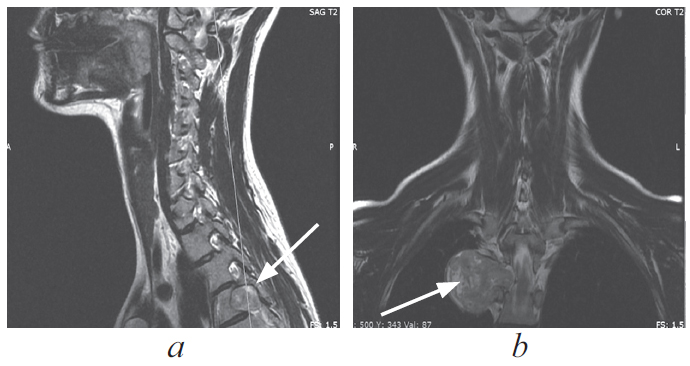

Paravertebral tumors of mediastinal localization — an extensive group of pathological processes, the surgical treatment of which is carried out by doctors of various specialties, such as neurosurgeons and surgical oncologists. Currently, thoracoscopic removal is considered to be the most preferred method of surgical treatment of these mass formations, in view of the least trauma, fewer complications, and a reduction in the time of postoperative recovery of patients. A clinical case of surgical treatment of a patient with a giant paravertebral tumor originating from the 4th thoracic root is presented. The tumor was an incidental finding during routine fluorography. There were no focal neurological symptoms. Taking into account the topographic and anatomical features of the volumetric formation, the patient underwent a combined two-stage surgical intervention, where the first stage was laminectomy and removal of the foraminal component of the tumor from the posterior approach, the second stage was single-port video-assisted thoracoscopic removal of the mediastinally located tumor fragment. The operation was performed under conditions of a collapsed lung on the side of the intervention. In the postoperative period, no neurological deficit was noted; according to the control introscopy, the tumor was removed completely. According to the results of histological examination – neurofibroma (Grade I).